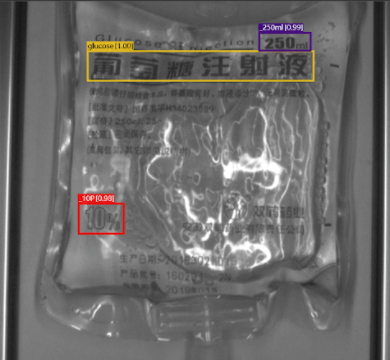

Classification

Glucose and Sodium Chloride Solution